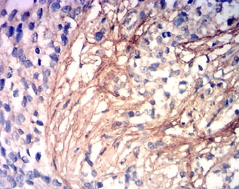

COL3A1 Mouse Monoclonal antibody[8C1G1]

This gene encodes the pro-alpha1 chains of type III collagen, a fibrillar collagen that is found in extensible connective tissues such as skin, lung, uterus, intestine and the vascular system, frequently in association with type I collagen. Mutations in this gene are associated with Ehlers-Danlos syndrome types IV, and with aortic and arterial aneurysms. Two transcripts, resulting from the use of alternate polyadenylation signals, have been identified for this gene.

Immunogen:    Purified recombinant fragment of human COL3A1 (AA: 24-153) expressed in E. Coli.

IHC    1/200 - 1/1000